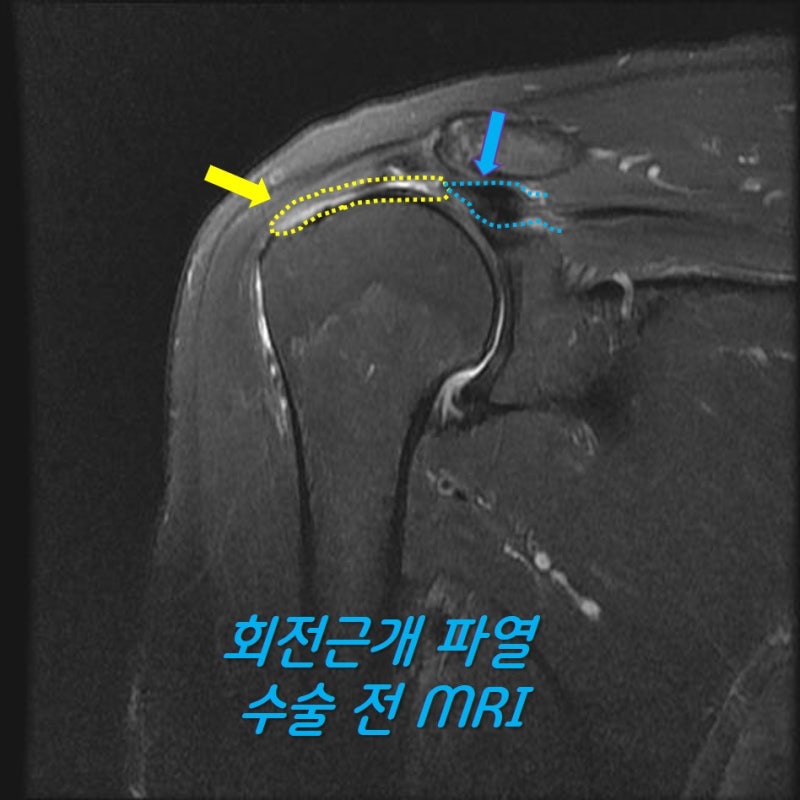

이학적 검사나 x-ray 소견상 회전근개 파열이 상당히 많이 의심되어 MRI 검사를 시행하였습니다.

이러한 경우 회전근개가 원래 상완골의 대결절까지 복원이 되어야 하는데 그렇게 되지 않을 가능성이 많습니다. 그래서 환자분의 수술 계획은 최대한 봉합술을 시행하고 복원되지 않는 부위는 인조인대(allomend)를 이용하여 보강하기로 계획하였습니다.